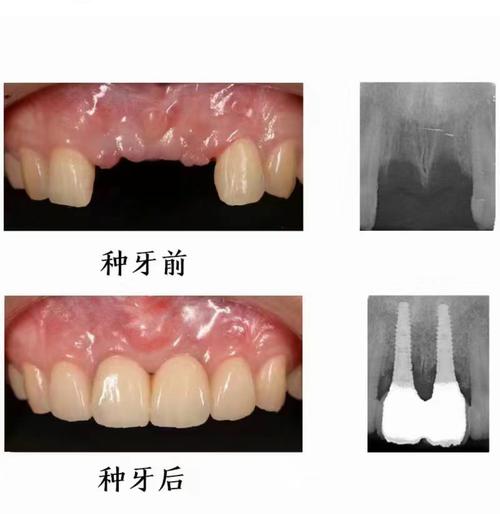

- 种植牙的本质: 种植牙是通过外科手术将人工牙根(种植体)植入牙槽骨中,待其与骨组织牢固结合(骨结合)后,再在种植体上安装牙冠,它模拟的是天然牙根的功能。

- 无牙周膜: 天然牙周围有牙周膜,这层富有弹性的组织允许牙齿在受到轻微力量时发生生理性移动(正畸利用的就是这个原理)。种植体与骨组织是直接结合的(骨结合),没有牙周膜,因此它本身无法被正畸力量移动。 试图移动种植牙会导致种植体周围骨组织破坏,最终导致种植失败。